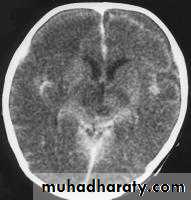

Bacterial Meningitis with cerebral oedema

Bacterial Meningitis with suppuration